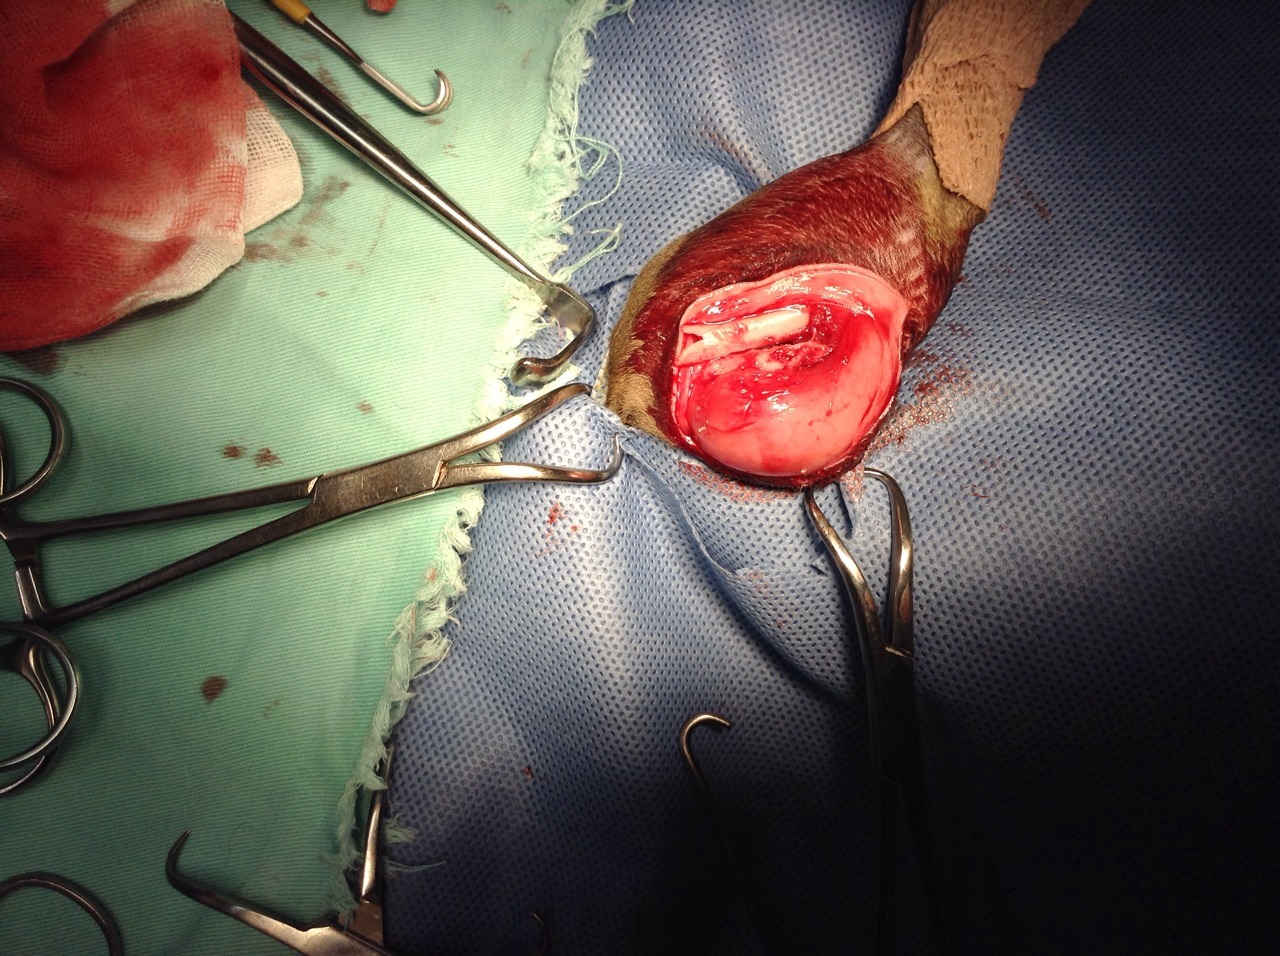

主題: 小灰灰 大腿骨折 申請者姓名: 程修玲 花色: 申請日期: 2013-11-05 07:36:20 申請者部落格: 申請者臉書網址: 所在縣市/合作醫院: 新北市/新北動物醫院 治療費用: 5000元 需求人數: 6人 已結案 (2014-01-10 17:54:23) 報名人員: 錢快來(已付款)、李采庭(已付款)、Tiffany Chang(已付款)、Bear(已付款)、柯元傑(已付款)、Janett Wang(已付款)、 候補人員: Hui Chung Shee、 動物病情說明: 說真的 這隻小灰灰會出現在汐止水蓮社區 讓愛媽很洩氣 因為社區愛媽 先前花了 快三年的時間 將社區裡頭近一百隻的浪浪都結紮了 現在竟然出現小灰灰 而且才兩個月 因為最近社區已結紮的浪貓 常為了地盤而叫囂 小灰灰可能為了躲避從近三層樓高的花台墜落而摔斷腿 一樓住戶原本要通報收容所 被我們攔截下來 花了一天一夜的時間誘捕 終於讓小灰灰入籠 經x光看到他的右大腿骨已經摔到錯位了 雖然他還小 其實開刀打麻醉有風險 可是不開他一定癱瘓 經討論之後 還是決定讓他開刀 希望能恢復他的大腿功能 動物近況說明: 小灰灰送醫後兩天後開刀 但術後恢復狀況不佳

用kid驗之後 出現初期貓瘟反應

最後回天乏術 請大家發揮愛心 送小灰灰最後一程 謝謝